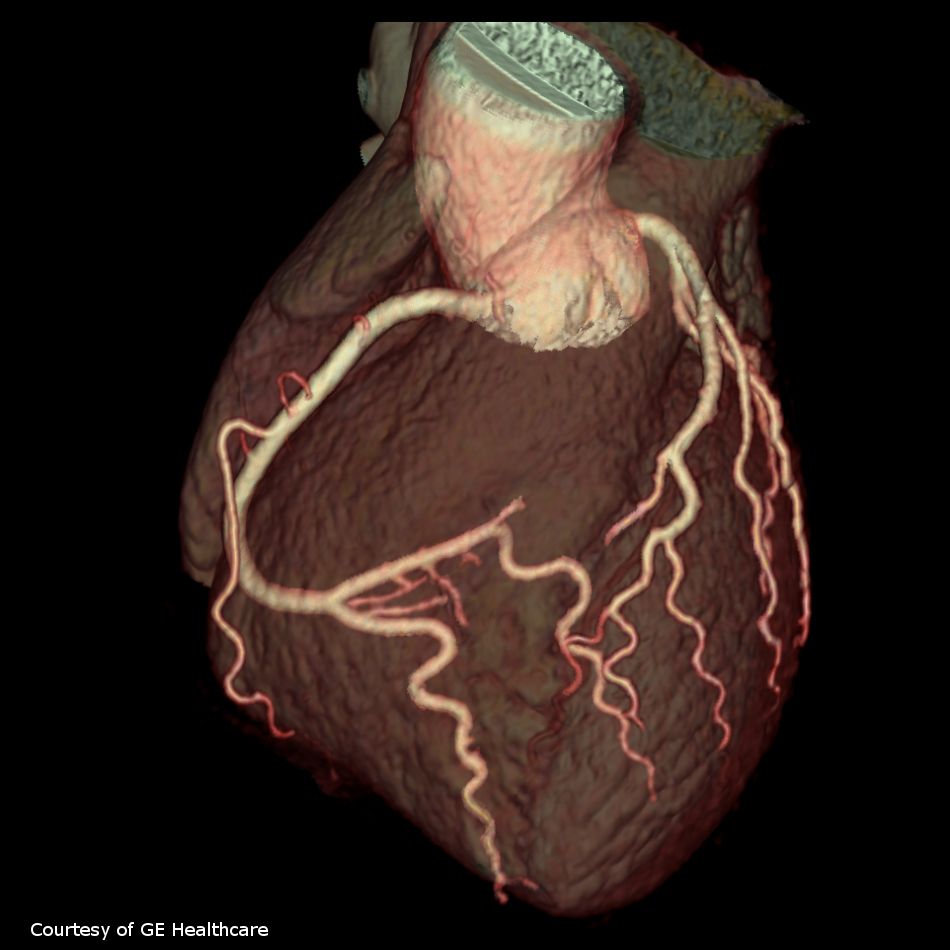

- является неинвазивным методом визуализации артерий сердца

КТ-коронарография назначается для решения следующих задач:

- оценки проходимости артерий сердца, с определением степени их сужения;

- оценки степени поражения коронарных артерий атеросклеротическими бляшками;

- поиск причины загрудинной боли;

- при подозрении на аномалию развития коронарных артерий.